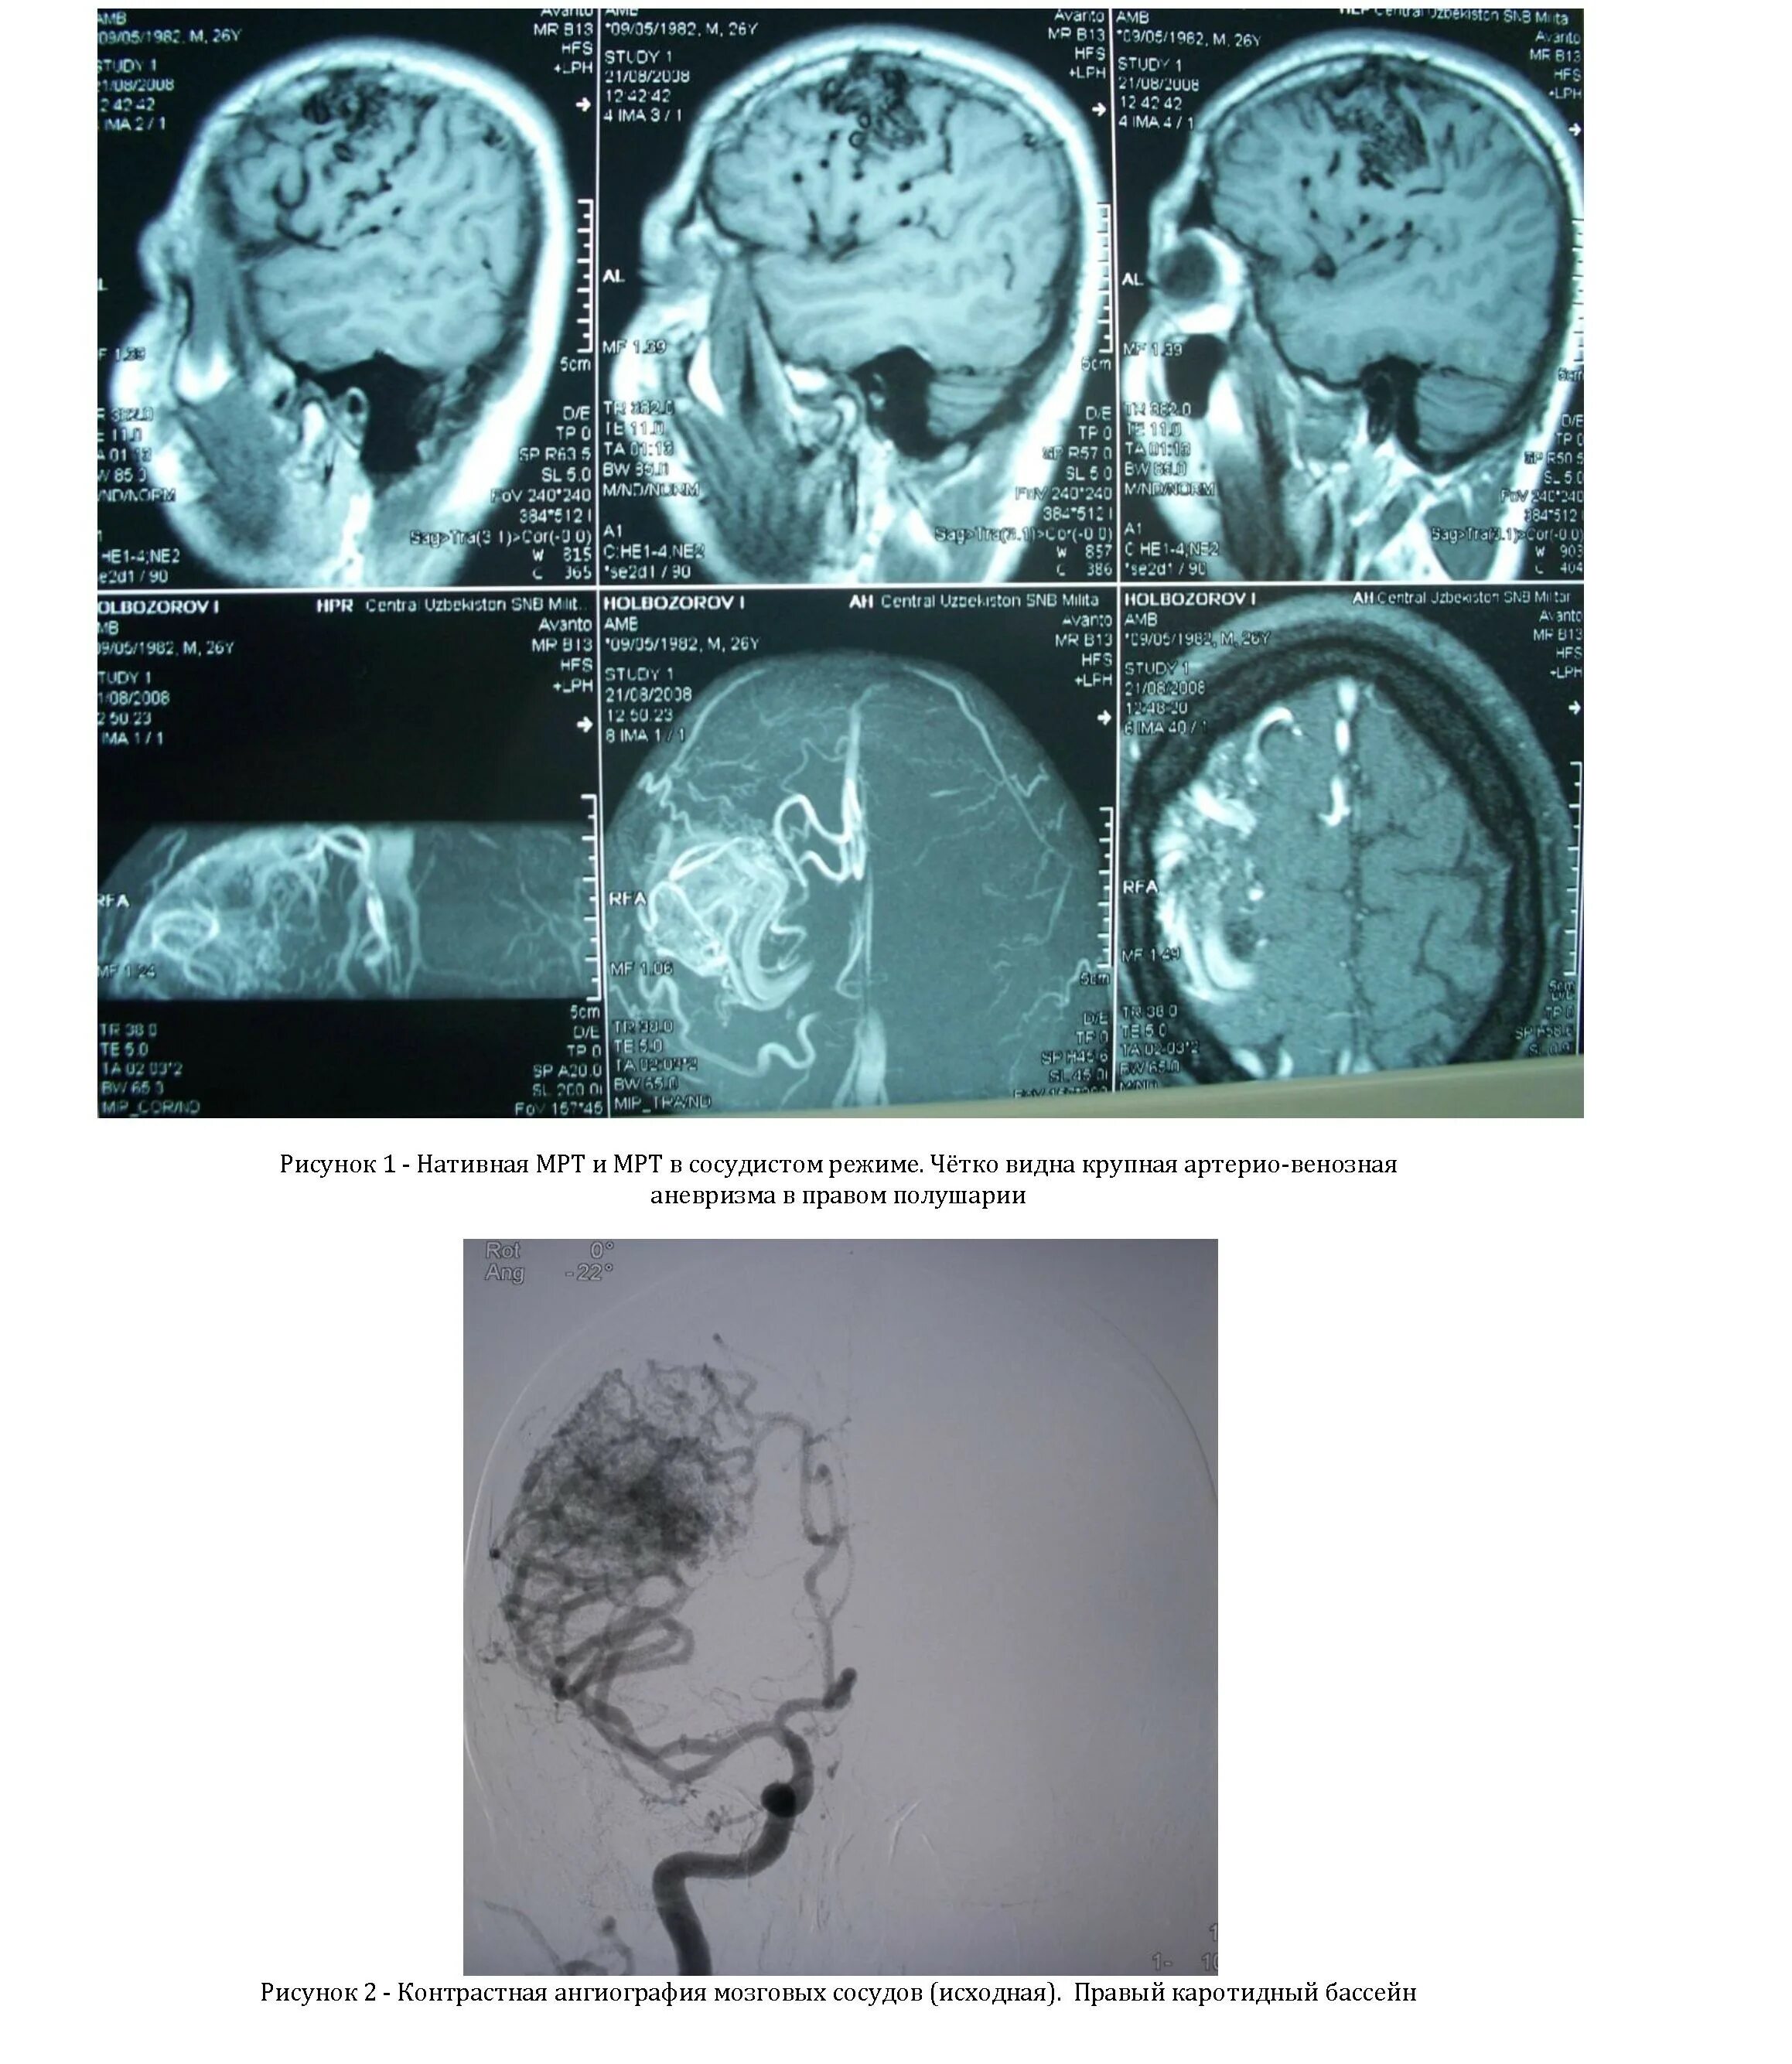

Что такое мальформация головного мозга